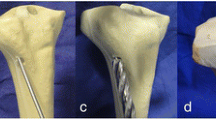

Sixteen Sawbones (left-side, medium size, item #3401, Malmö, Sweden) were implanted with a Medial Distal Tibial Plate (MDTP; Synthes, Switzerland; n = 8) or a DTN (n = 8) and a Medial Wedge Opening (MWO) osteotomy simulated at 45 mm proximal from the distal articular tibial surface. A brief description of the DTN and MDTP implantation procedures can be found in Kuhn et al.14 and AO Foundation surgery reference17, respectively. Screw insertion for both implants is conducted through small incisions in the skin using a scalpel. The wedge was 10 mm in height and left 5 mm of lateral cortex intact (Fig. 1a). This was known as “best-case scenario” SMOT where the lateral cortex is fully intact. Following a first round of biomechanical testing (explained below), “worst-case scenario” SMOT was simulated where the lateral cortex of all samples was cut using a 0.5 mm coping saw. This latter phase replicated a fracture of the lateral cortex, which can occur during the surgical procedure. In true surgical situations, the distal tibia is prized open to create a wedge-shaped gap; in our study, a wedge of composite bone was cut from the distal tibia using a manual saw. The fibula was omitted from all tests due to complications relating to the inclusion of an inter-osseous membrane connecting the tibia and fibula18. In vivo, this membrane is primordial for the force transmission between the tibia and fibula, however no composite structure to date has been developed to replicate this phenomenon.

All samples were subjected to extra-axial compression tests13,14 of 350 N at 0.1 Hz followed by 700 N at 0.05 Hz with an 18 N compressive pre-load applied. For compression testing, the samples were placed in a double ball-joint setup (Fig. 1b). The proximal loading point was considered to be at the physiological loading axis taking into account the 60/40% medio-lateral load distribution across the tibial plateau21,22,23, located at 10 mm medio-posterior to the central axis, generating a lever arm of 14.14 mm. The distal ball-joint was placed in the central axis of the Sawbones samples. Following this, torsional tests of ± 4 Nm at 0.1 Hz, and ± 8 Nm at 0.05 Hz were performed, no torsional pre-load was applied to the samples; however, a 6 N compressive load was applied throughout all torsional testing to ensure sample stability in the test setup. Torsion tests were carried out by proximally and distally clamping the sample in the testing machine. The proximal PMMA was set in the inferior joints and the distal end of the sample was clamped in a detachable PMMA block in the superior joints (Fig. 1c). All tests were conducted over 30 cycles. Fatigue testing at 1000 + cycles was not chosen for this study as the aim was to carry out a preliminary investigation into the bone-implant construct behaviour. Machine data was recorded at 25 Hz, still camera images were recorded at 10 Hz. The machine and camera data acquisitions were synchronised using a trigger sent by the testing machine at the start of testing.